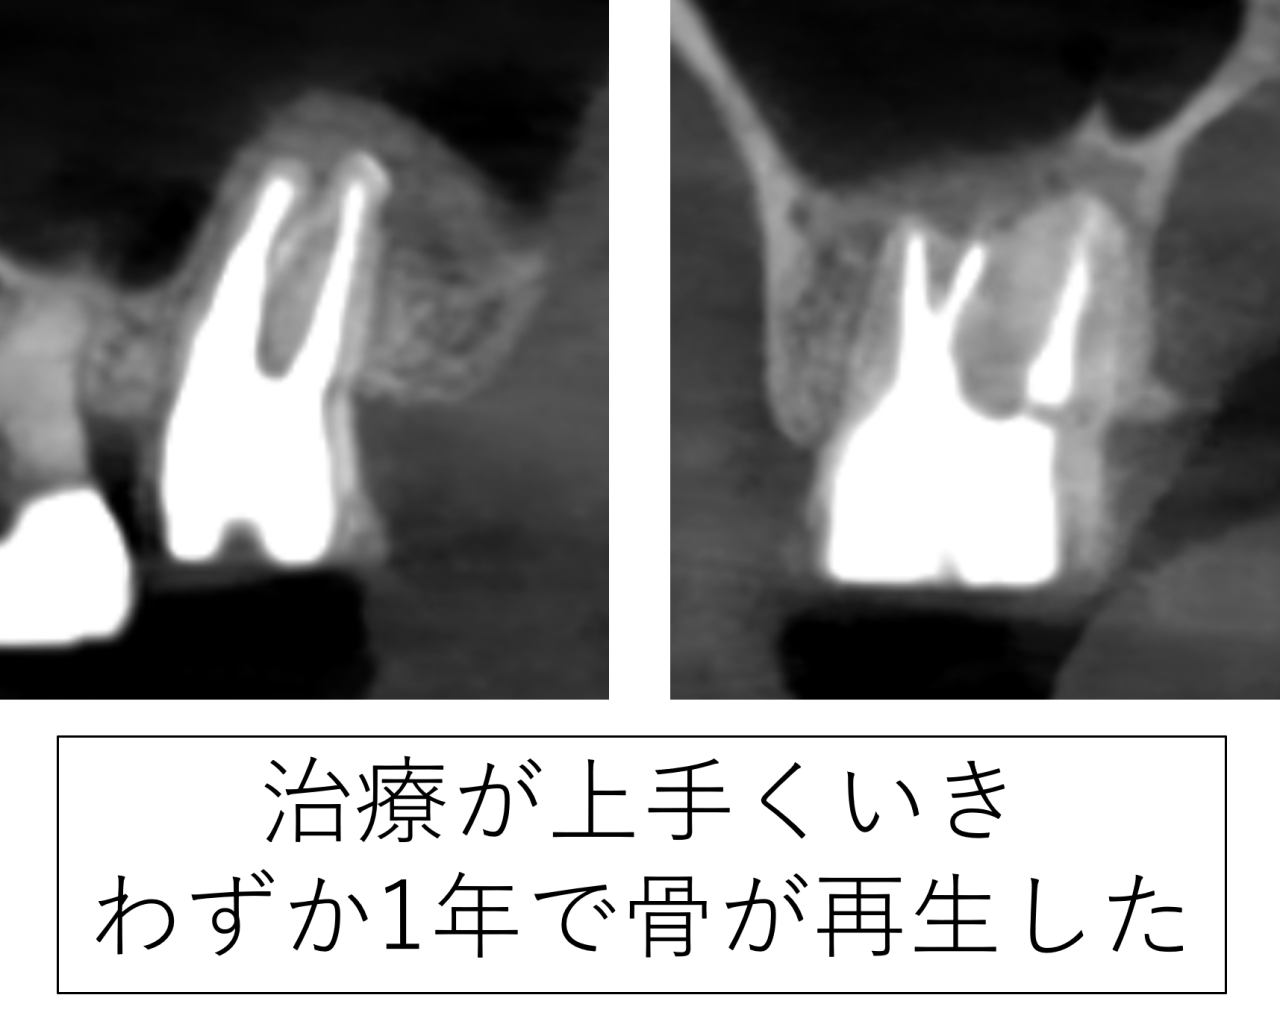

1年後に確認できた骨の回復(再生)

治療が終わったからといって、それで終わりではありません。内部がどのように回復しているかを確認することが重要です。

治療から1年後にレントゲンで経過を確認したところ、以前は大きく写っていた病巣(骨の吸収像)が縮小し、周囲の骨の回復(再生)が確認できました。1年での回復とても早いです。患者様はとても喜ばれました。

骨には回復する力があります。ただし、その前提は炎症の原因が取り除かれていることです。原因が残っている場合、回復は起こりにくいです。

骨を回復するのは患者様の免疫力です。根管治療はあくまでもそのお手伝いです。今回の症例では、感染源を適切に除去できたことで、体の免疫・治癒反応が働き、良好な経過が得られました。